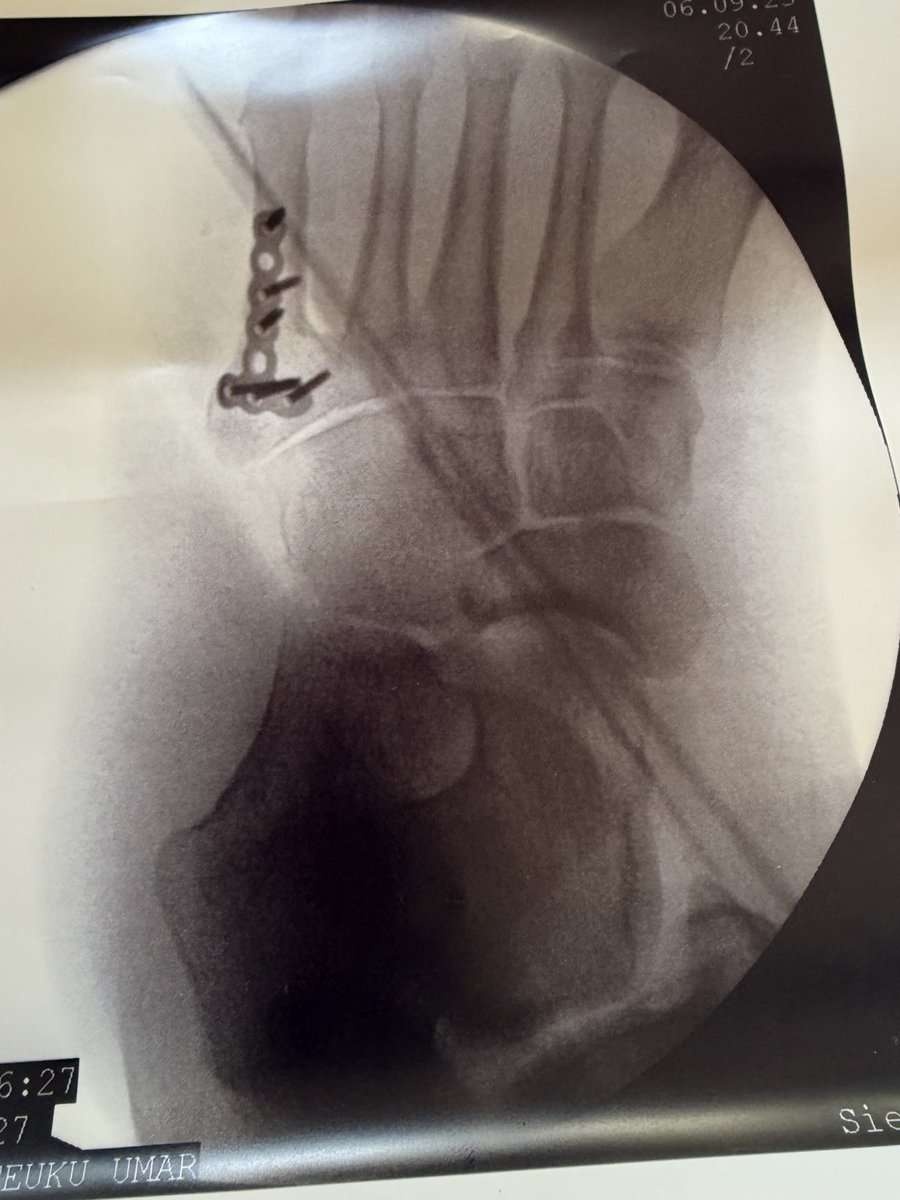

星乃うめ 骨折して療養中 @hoshino_ume_ 9月11日

バリ島で骨折してしまったのでそのまま入院して左足にボルトを入れました…

拒否権がなくすぐに緊急手術になってしまい本当に不安で怖くて…入院生活楽しめなかったので海外でもう絶対に事故ったりしないようにしたいです(><)

レス3番の画像1